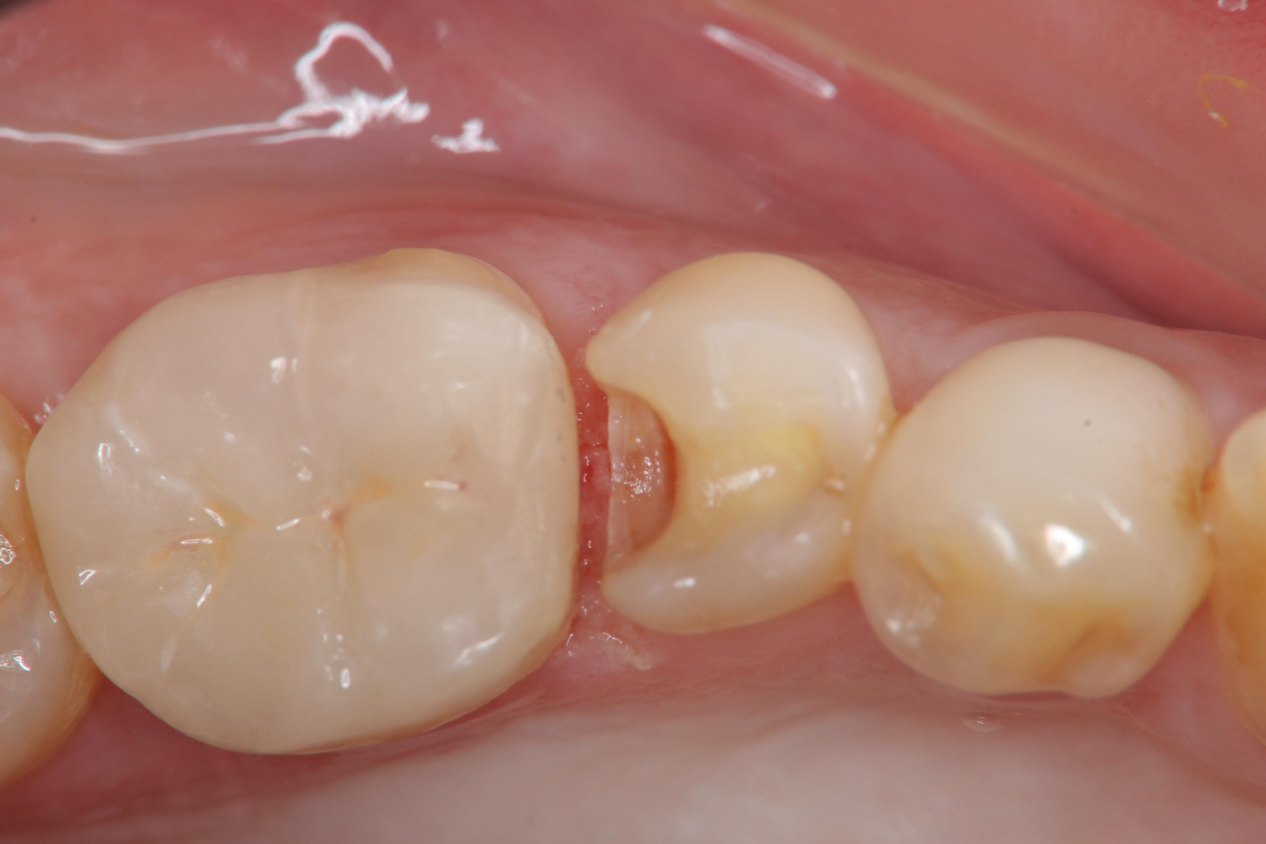

治療前,小臼齒變色

二次蛀牙,牙髓未受侵犯

崁體窩洞製備